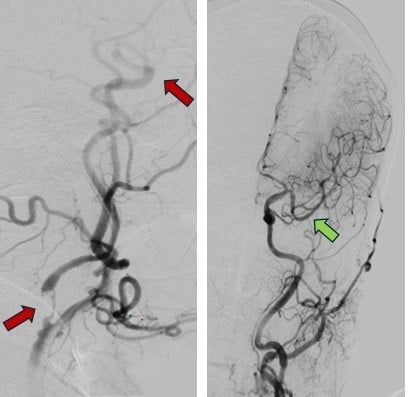

Thủ thuật can thiệp mạch não lấy huyết khối trong cửa sổ điều trị mở rộng lên đến 24 giờ giúp tái thông mạch máu và cứu sống người bệnh đột quỵ

Hình ảnh mạch máu bị tắc (mũi tên đỏ) và

sau khi được tái thông hoàn toàn (mũi tên xanh)